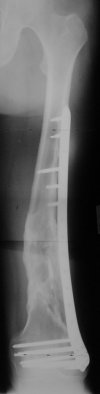

THX, initial images are

1,

2.

At that moment we had in stock only the 10 mm solid nails so of course there was no idea about early weight bearing. But it was quite enough for early knee ROM excersises (see attached). Two locking screws through the distal block provided that.